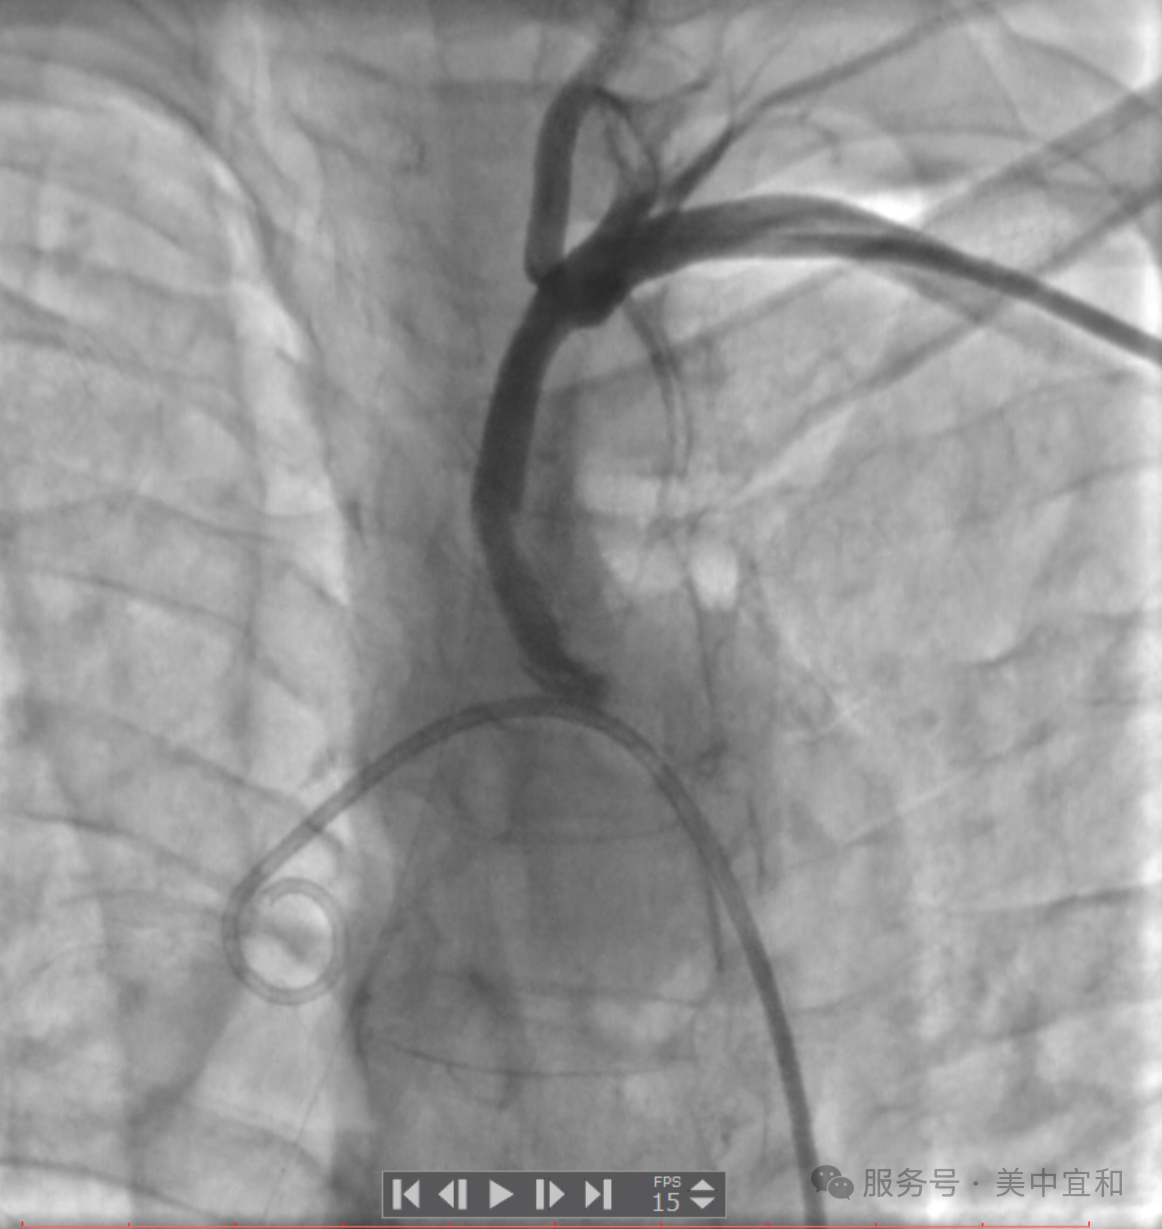

明确诊断后,经过心内科团队的反复讨论,为患者制定了缜密的介入治疗计划。最终,经过近 2 个多小时的手术,成功逆向开通血管并植入支架,术后患者双上肢血压恢复一致,左侧椎动脉供血良好,眩晕症状明显改善,悬着的心也终于放下了。